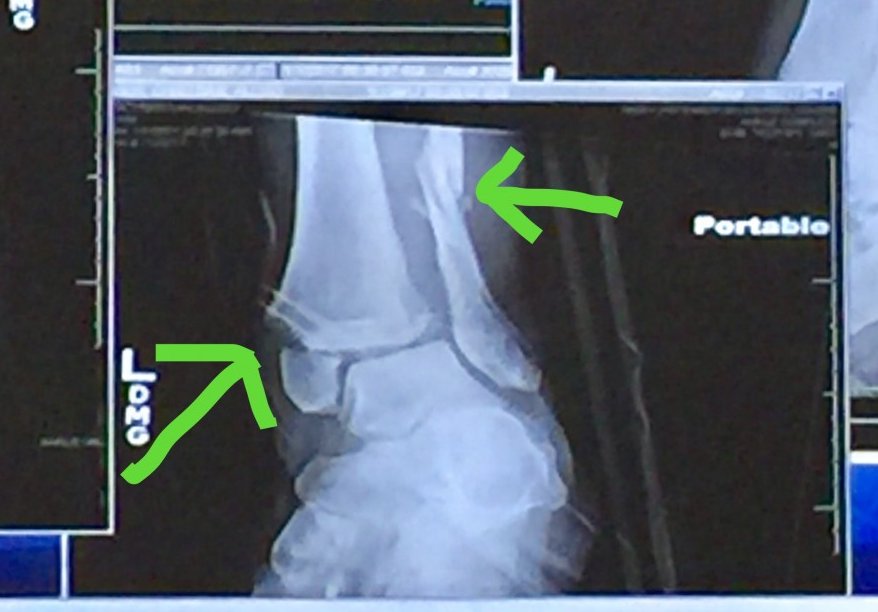

Unfortunately, I misjudged the distance between myself and the deer and caught it with my foot. Hitting a deer with your leg at 65 MPH, is not a pleasant experience and I don't recommend anyone try it. I wound up breaking my leg in four places and dislocating my ankle.

I'm doing much better now. I had surgery to have a large plate put on my fibula, which was snapped. The plate is held in by eight screws. I also had a small plate put on my tibia and two screws put through my ankle.